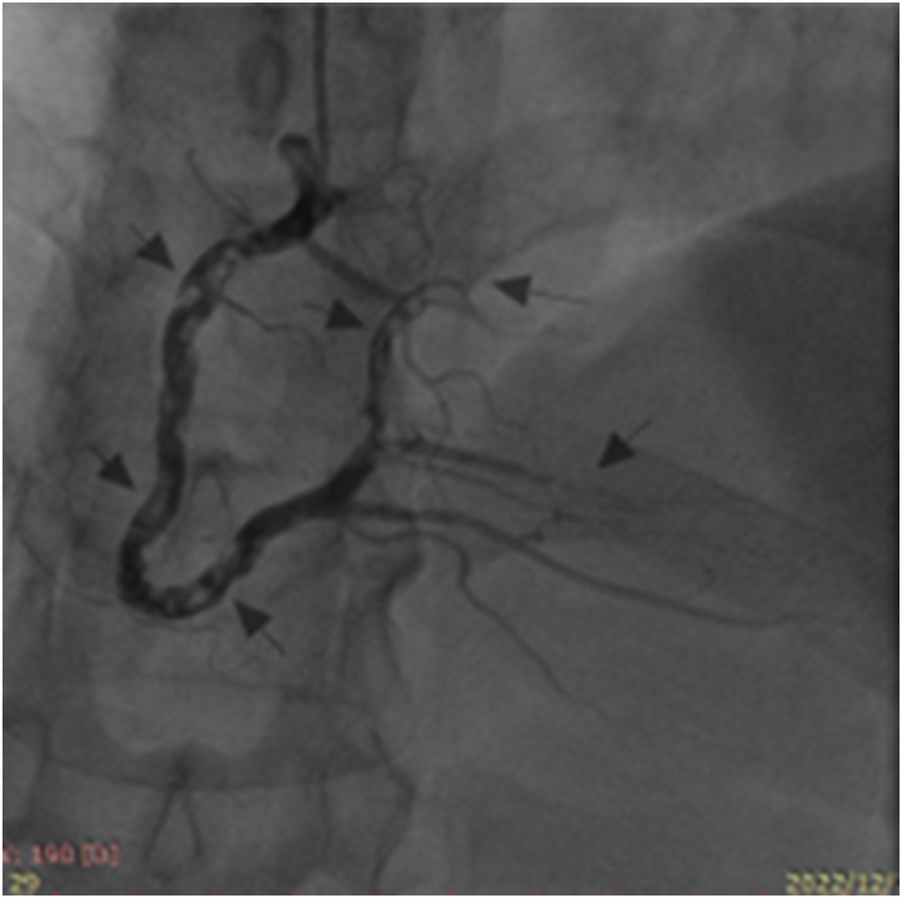

We repeated coronary angiography on December 13, 2022, and no significant abnormalities were observed in the left coronary artery. However, diffuse thrombosis was present throughout the right coronary artery, in addition to occlusion of the distal PLB and its first branch (Figure 2). TIMI 3 flow was achieved after an intracoronary arterial injection of tirofiban (10 μg/kg). Postoperatively, tirofiban was continuously infused at a rate of 0.15 μg/kg/min for 24 h. The patient was subsequently prescribed long-term oral clopidogrel 75 mg and rivaroxaban 15 mg once daily. Repeated examinations revealed a significant decrease in the cardiac troponin I level, which gradually returned to normal (Table 1). He was discharged and followed up in the clinic.

Figure 2

Second coronary angiography revealing diffuse thrombosis throughout the entire right coronary artery and occlusion of its distal posterior left ventricular branch and first branch (arrows).